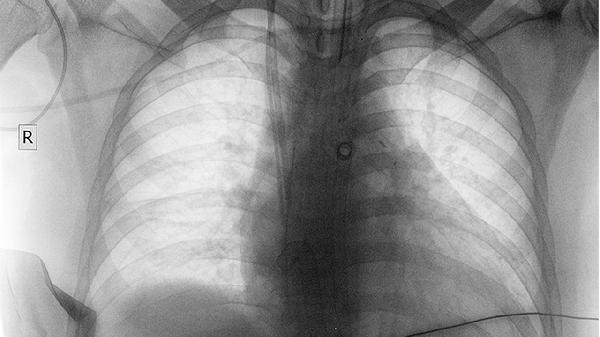

4、鼻癌虽然罕见,但若干血痂伴随持续鼻塞、单侧鼻出血、面部疼痛或嗅觉减退等症状,需警惕。鼻癌早期症状不明显,确诊需通过鼻内镜检查、CT或活检。及时就医排查,早期治疗可提高治愈率。